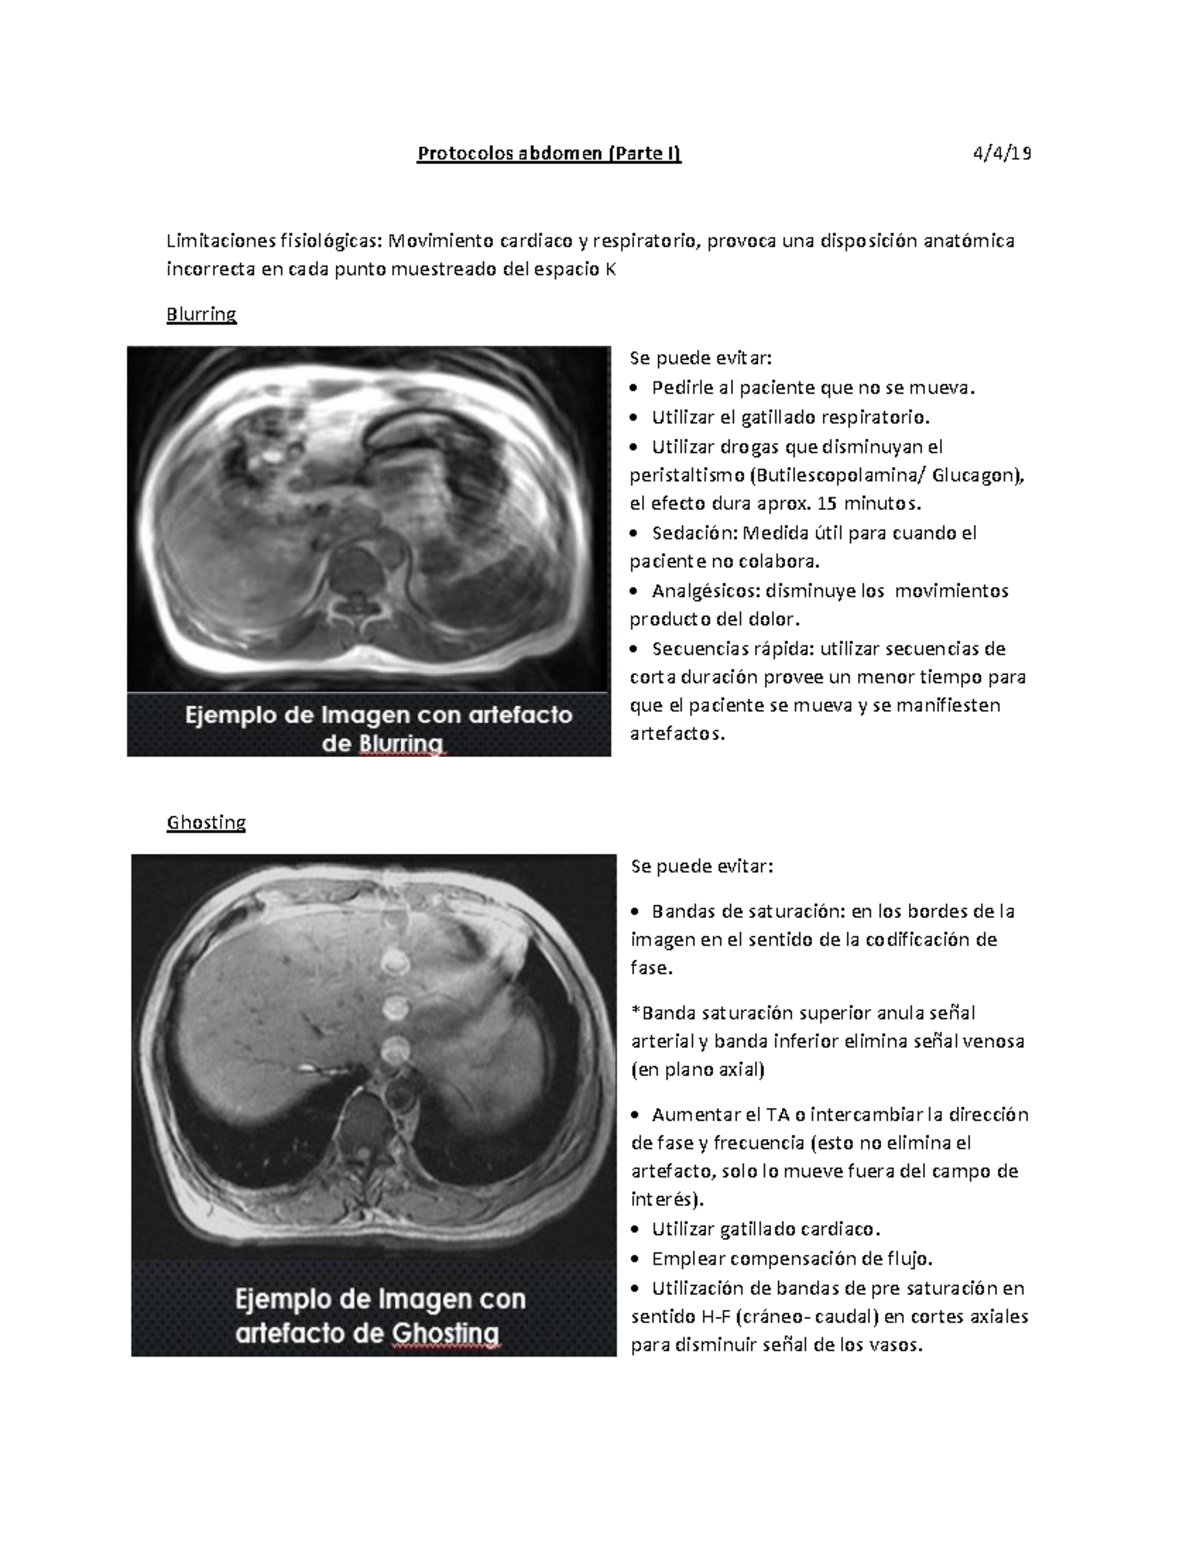

06 Protocolos abdomen higado Protocolos abdomen (Parte I